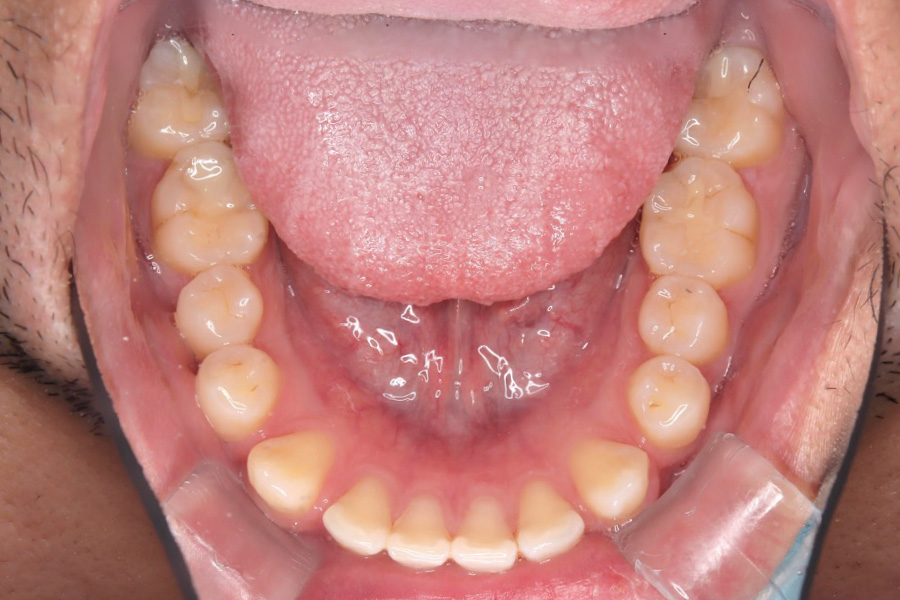

【20代男性】

歯の隙間を

インビザライン矯正で治療したケース

治療後

主訴 歯の隙間が気になる

治療内容 インビザライン矯正

非抜歯

治療に伴うリスク 矯正終了後は、リテーナーを指示通りに使用し、歯の後戻りを防ぐ必要があります。